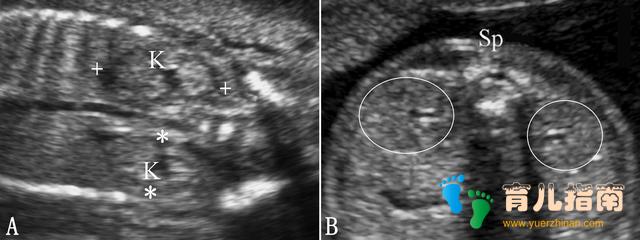

3. 肾脏测量 包括肾脏长度(FKL)和肾脏体积(FRV)测量(图1)。FKL与胎儿体重有很好的相关性。FRV也与胎儿体重有关。在IUGR中,FRV也可以作为胎儿体重的评估指标。

图1胎儿肾脏测量